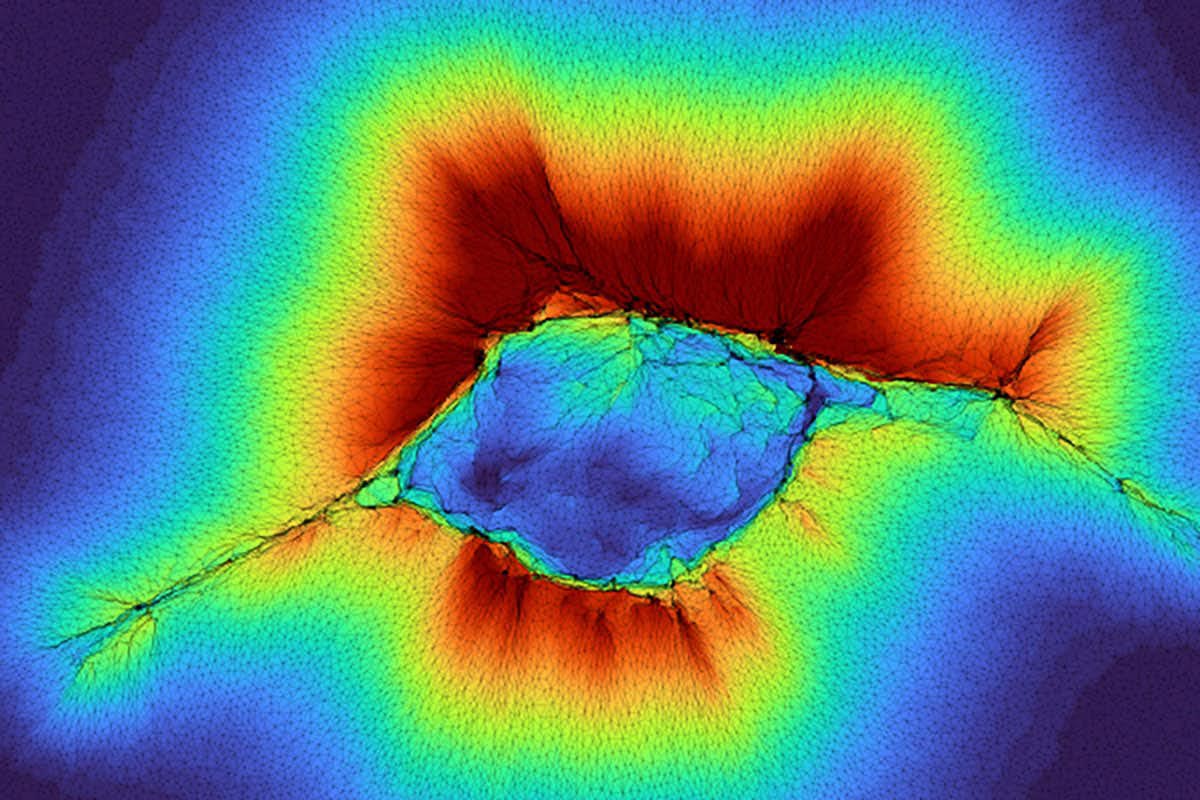

У цій моделі клітинні кластери можуть «відчувати» те, що знаходиться далі за межами їхнього оточення в людському тілі, діючи як колектив, що тут показано як «простягання руки», де червоний колір позначає просторовий розподіл деформації колагену над шаром жорсткої тканини. Дослідники з Вашингтонського університету діляться деталями про цю нову властивість у журналі PNAS. Джерело: лабораторія Патака

Нове дослідження доводить, що групи звичайних клітин можуть «бачити» ще далі — до 100 мікрон. Патак пояснює: «Оскільки це колектив клітин, вони генерують більшу силу». Кластери проходять дві фази — згуртування та міграцію — і саме їхня здатність відчувати структури під поверхнею визначає напрям руху. Змінений розподіл напружень у колагені формує шлях для пересування клітин.